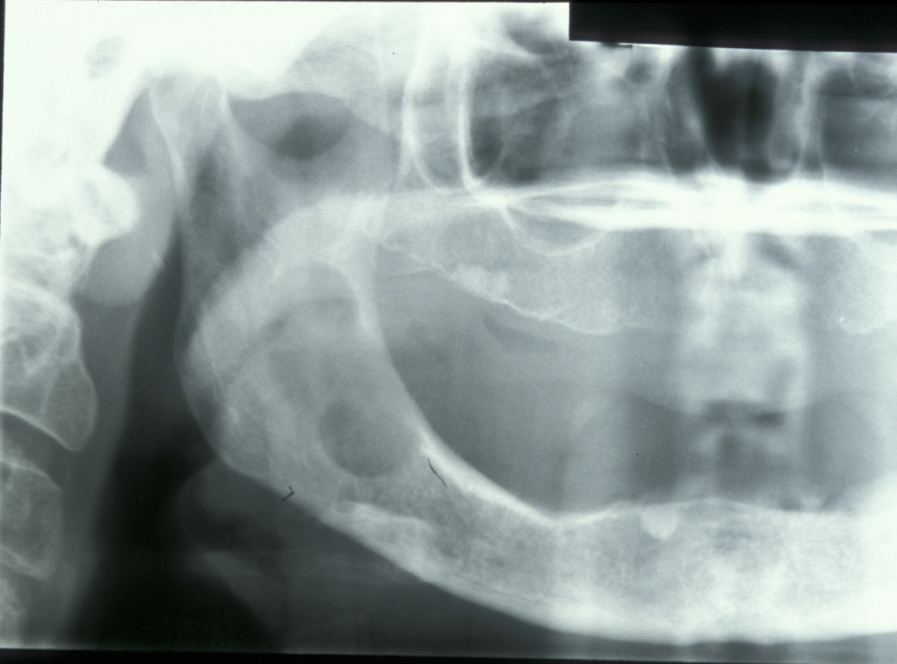

Limited resection represents a more aggressive form of removal of a cyst in that it will include the removal of bone in the vicinity of the cyst (a modified enucleation). It may also be a rim resection of the mandible (where a considerable portion of the mandibular bone is removed but a thin rim of the mandible is preserved to provide continuity of the bone). Treatment with Carnoy’s solution (a mixture of 60% alcohol, 30% chloroform and 10% concentrated acetic acid; applied locally directly after enucleation of a keratocyst) is popular with some surgeons. This is a way to reduce recurrence of keratocysts: the epithelial lining in keratocysts is very friable and therefore difficult to remove completely. Cryotherapy (local use of low temperature) may also have a role. A resection procedure with a reinforcing reconstruction plate is illustrated in Figures 10 to 15.

Figure 10: A large keratocyst, requiring more radical excision.